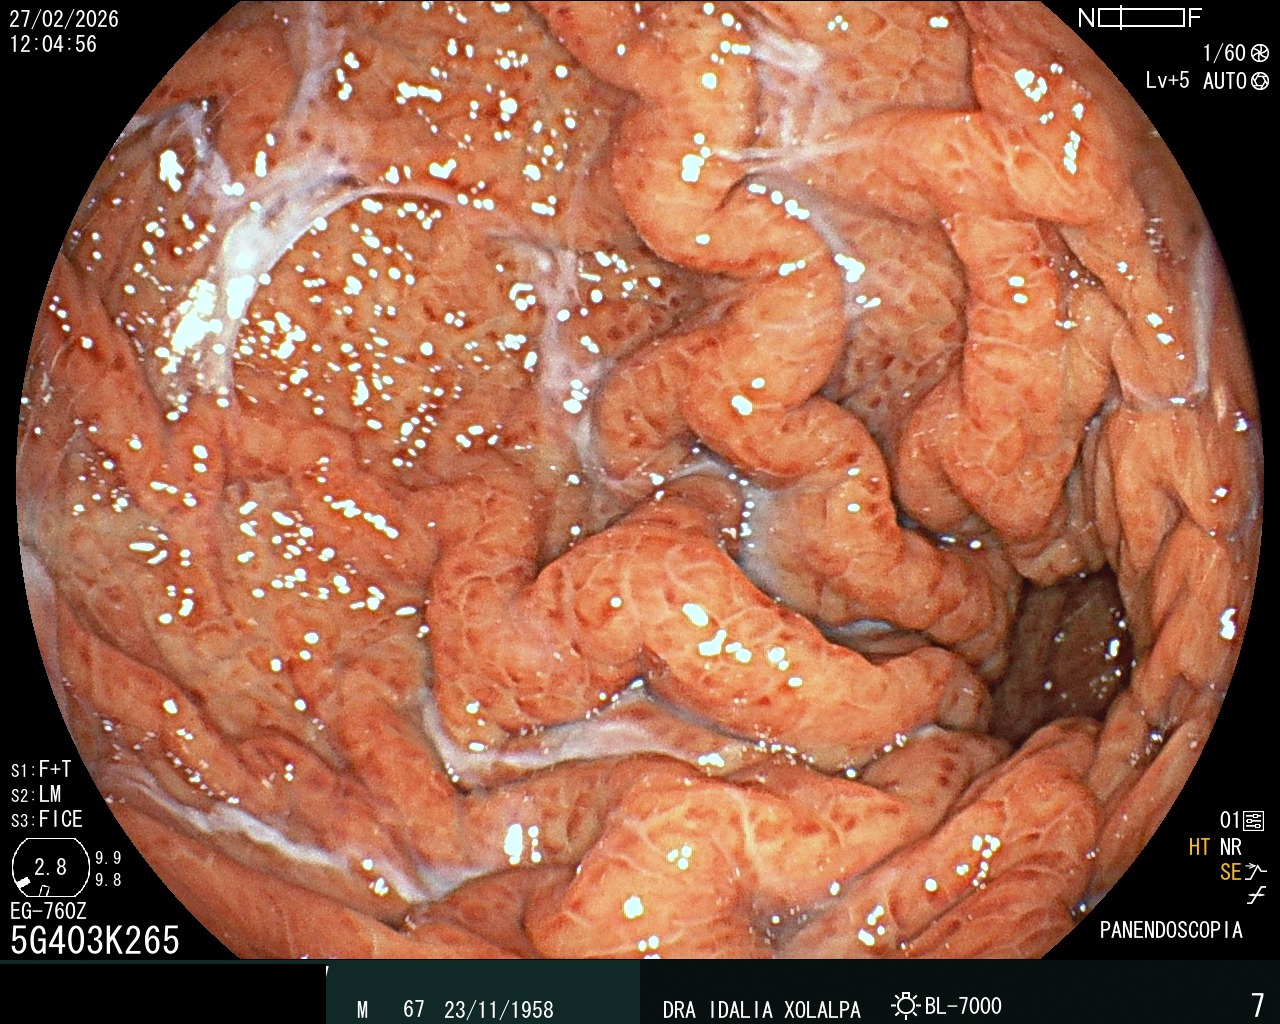

Gastritis Severa

Hallazgo de gastritis durante panendoscopia